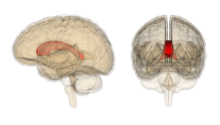

What happens to the brain when you meditate?

- Sensory Cortices and Insula: Bodily sensations such as pain and touch. Emotional and cognitive awareness

- Hippocampus:Memory consolidation and reconsolidation

- anterior cingulate cortex: Concentrative solving of problems, self-control and behaviors which are adaptive during altering circumstances

- Mid cingulate cortex: Concentrative solving of problems, self-control and behaviors which are adaptive during altering circumstances, and higher scores in EA

- orbitofrontal cortex: Analysing stimuli and determining the correct motivational actions ,ER, EA and specifically in lessening reactions and in reappraisal.

- Superior Longitudinal Fasciculus:spatial awareness and the ability to perceive in 3D.

- Corpus callosum: Inter and intra hemispheric communication. Acts as an connection highway for various other regions of the brain including frontal brain areas with visual cortices at the back of the brain.

(Fox et al., 2014 p. 48)

- Grey matter regions

- Anterior cingulate cortex

- Posterior cingulate cortex

- Insular cortex

- Temporoparietal junction

- Cerebellum

- Hippocampus

- Caudet nucleus

- White matter pathways

- Superior longitudinal fasciculus

- Saggital Stratum

- Thalamic radiation

- Corona radaite

(Ospina et al, 2008, p. 1199)

Studies have shown that those who regularly practice meditation undergo brain morphometry; changes to brain structure, dimensions, arrangement of fibres, volume and density including measurements of grey and white matter (Fox et al., 2014 p. 52). Brain morphometry can be seen even after just brief periods of meditation on beginners (Ospina et al, 2008, p. 119), while long term meditators show significant alteration in various regions of the brain (Krygier et al., 2013, p. 306).

Regular meditators have higher than average density in brain regions that are active during meditation, including right orbito-frontal cortex, right hippocampus, right anterior insula and inferior temporal gyrus. The cortices, insular and prefrontal cortices are thicker in the brain of those who practice regular meditation (Krygier et al., 2013, p. 306). Meditation has also been shown to increase the amount of alpha and theta waves waves in the brain (Sobolewski et al., 2011, p. 44)